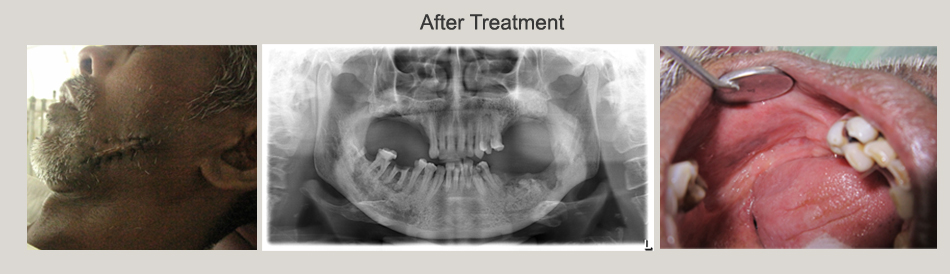

Osteoradionecrosis